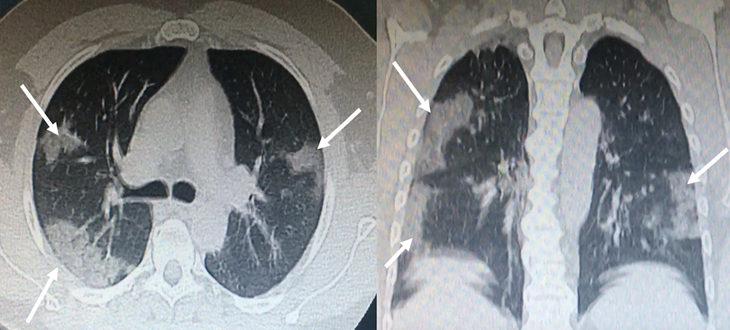

Ground glass opacities on chest computed tomography (CT) and bilateral infiltrates with a tendency for consolidation (Fig. 1). The patient signed an informed consent to receive plasma transfusion.

Figure 1: Bilateral, subpleural ground-glass opacities suggestive of SARS-CoV-2 pneumonia